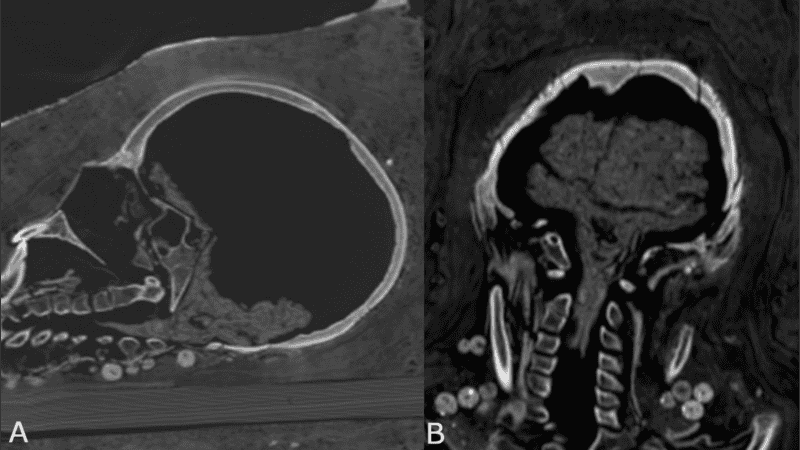

Mediante análisis de tomografía computerizada, los investigadores lograron obtener información sobre el estado de conservación de los cuerpos, la técnica de momificación artificial usada, la edad de los individuos en el momento de la muerte, así como su género, altura y salud.

"Las investigaciones radiológicas anteriores de las momias de los períodos romanos ya revelaron que algunas no mostraban evidencia de extirpación del cerebro y de los intestinos. La identificación del cerebro conservado en el caso de la mujer joven apoya, por lo tanto, esta idea", explicó a IFLScience, el investigador principal del estudio, Stephanie Zesch.

Este nuevo tratamiento fue posible identificarlo solo en la momia joven, pues los cuerpos del hombre y la otra mujer estaban "bastante mal conservados" y no se pudo determinar una técnica específica de momificación artificial.